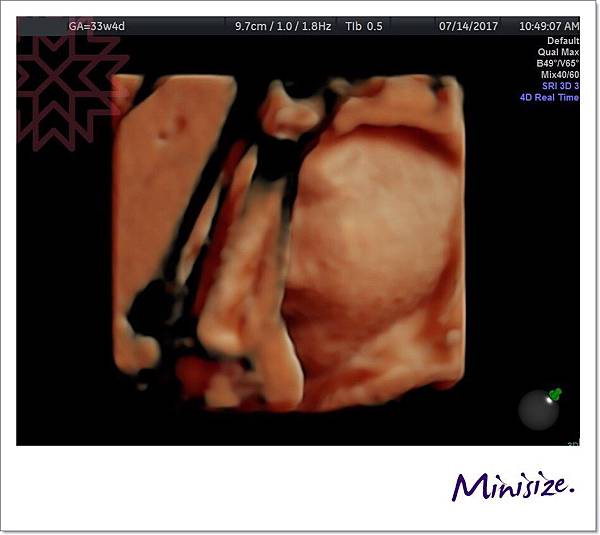

再來到了33週

Timo直接把臉臉用軟Q腳擋住

只剩下半邊肥肥臉蛋讓麻麻收藏了